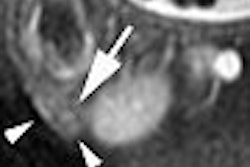

According to the MR results, the semimembranosus muscle was injured in 87% of the cases, as was the quadratus femoris muscle (also 87%). Eleven of the 13 semimembranosus muscle injuries showed a collar of high signal intensity around the thickened tendon, the authors reported. After six weeks, MRI signs of injury still remained for 10 of these dancers.

Eleven of 13 quadratus femoris injuries showed intrafascial and extrafascial edema. After six weeks, MR injury signs remained for six subjects. In addition, one out of five adductor magnus injuries persisted over the long term. Finally, changes in length, width, and depth of sustained injuries ranged from 7% to 52% over six weeks.